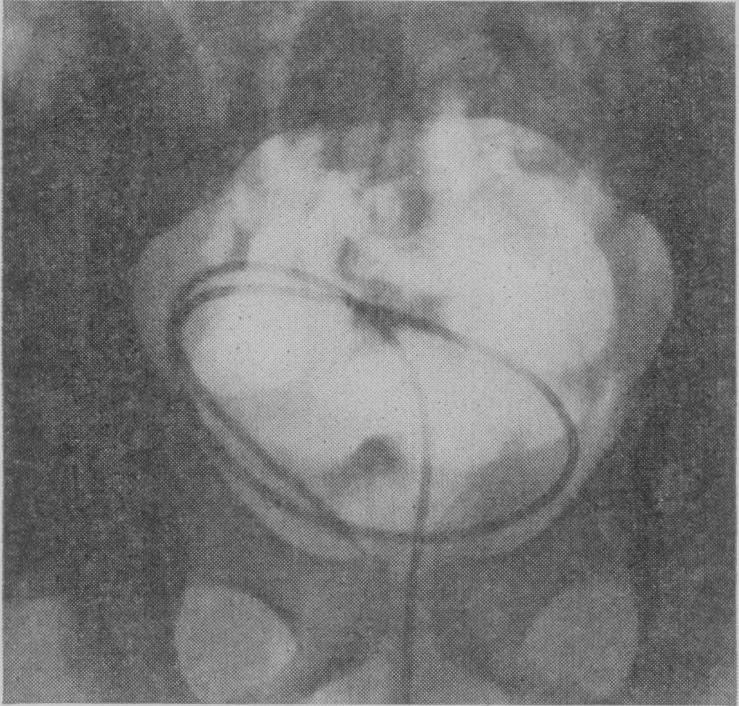

BROWN J J M

Proc R Soc Med. 1956 Nov;49(11):891-4. doi: 10.1177/003591575604901106.